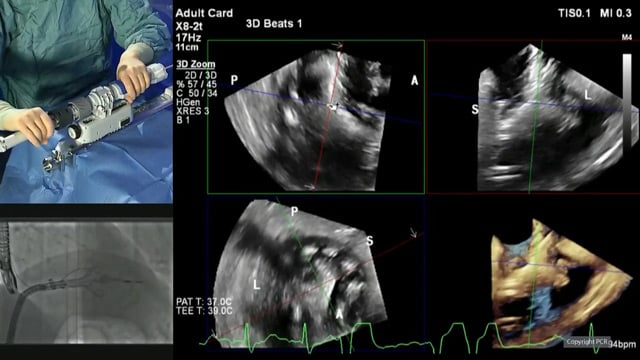

Mitral TEER: LIVE Educational Case from Hospital Álvaro Cunqueiro - Vigo, Spain

16 Nov 2025 – From PCR London Valves 2025

This live educational case from Hospital Álvaro Cunqueiro in Vigo, Spain, offers an in-depth look at Mitral TEER, including patient presentation, imaging analysis, operator strategy, and device overview. The session also features a recorded case from the Heart and Diabetes Center NRW in Germany, providing comprehensive...